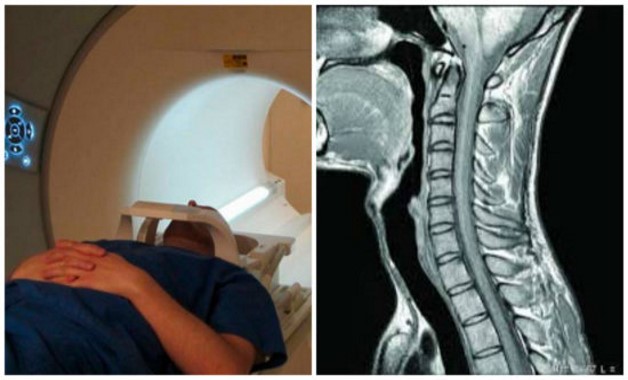

Диагностика заболевания

Рентгенография – не единственный метод, который помогает установить заболевание, поражающее позвонки шейного отдела позвоночника. Исследовать течение болезни и определить степень артроза возможно путем более точных и современных диагностических методов:

- компьютерной томографии;

- магнитного резонанса или МРТ.

Исследование позволяет:

- обнаружить остеофиты в шейных позвонках;

- установить степень поражения нервных окончаний и кровеносных сосудов.

На заметку. Чтобы исключить возможность других заболеваний, врач может направить человека на дополнительные медицинские консультации, например, к окулисту, кардиологу, нейрохирургу.